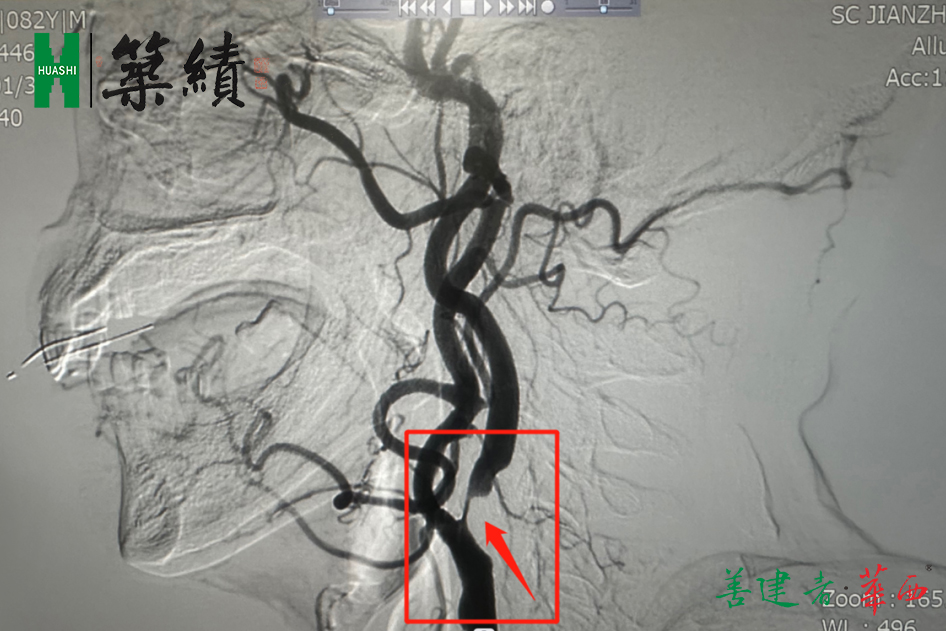

▲颈动脉狭窄行脑血管造影术

2023年1月,省建筑医院神经外科开展“颈动脉狭窄行脑血管造影术”、“三叉神经痛微血管减压术”两项新技术,充实院内诊疗项目。